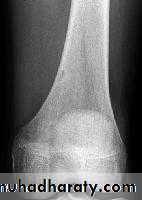

Benign bone tumoursFibrous cortical defect

= non-ossifying fibromaVery common

ChildAccidentally on XR

Pain or pathologic fractureNo malignant potential

Rx : curettage + bone graftOsteoid osteoma